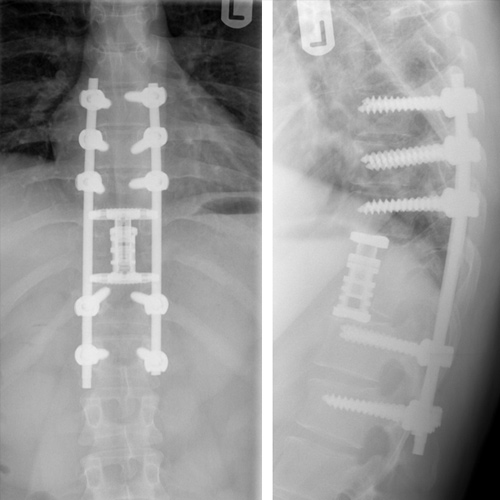

Spinal stenosis (Lumbar) Spinal stenosis (Cervical) Spinal stenosis (Thoracic) Lumbar Disc Herniation Spondylolisthesis Cervical Foraminal Stenosis Vertebroplasty Lumbar Fusion Anterior Cervical Fusion (ACDF) Posterior Cervical Fusion Thoracic Fusion Revision Lumbar Fusion Surgery Facet Joint Cyst Spinal Tumour Minimally Invasive Lumbar Fusion (XLIF) Minimally Invasive Lumbar Fusion (ALIF) Lumbar Fusion (TLIF) Thoraco-lumbar Fusion Lumbar Corpectomy Complex Lumbar Spine Surgery (Spino-pelvic fixation) Complex Cervical Spine Surgery Complex Thoracic Spine Surgery Occipito-cervical Fusion Minimally invasive surgery for thoracic disc herniation Other Related Topics